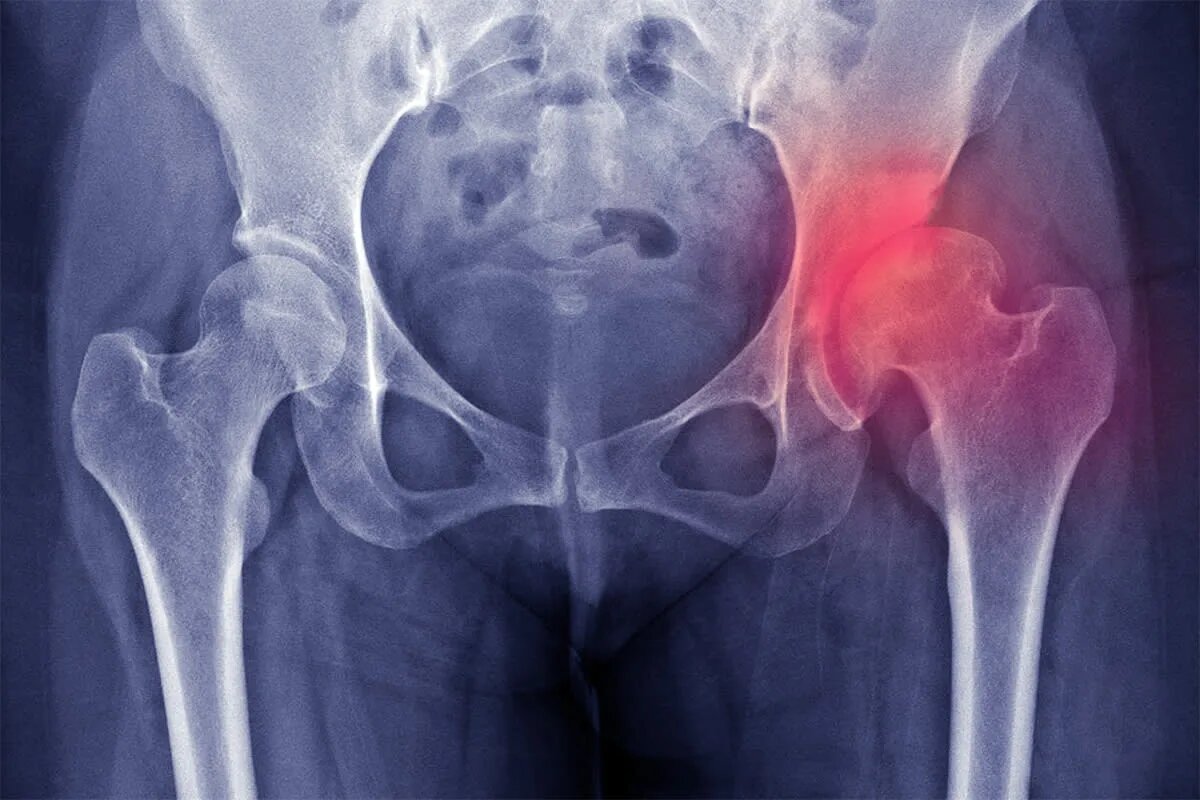

На рентгене уже видно сужение суставной щели на 30-50%, начинают расти остеофиты, головка бедра уплощается и деформируется.

На рентгене – практически полное отсутствие щели, огромные остеофиты, головка бедра напоминает гриб или наковальню, вертлужная впадина уплощена.

2. Рентгенография – главный метод. Делают снимок тазобедренных суставов в прямой проекции и в боковой. Рентген показывает:

Сужение суставной щели.

Остеофиты – костные шипы по краям сустава.

Склероз (уплотнение) кости под хрящом.

Кисты – мелкие полости в кости.

Деформацию головки и впадины.

Стадии коксартроза по рентгену (по Келлгрену-Лоуренсу):

• 0 стадия – нет признаков.

• 1 стадия – минимальные остеофиты, щель нормальная.

• 2 стадия – небольшие остеофиты, щель умеренно сужена.

• 3 стадия – умеренные остеофиты, щель выраженно сужена, склероз.

• 4 стадия – крупные остеофиты, щель почти не видна, деформация сустава.